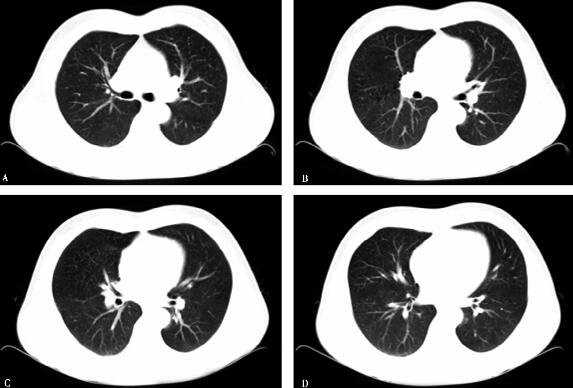

6.2010年4月20日胸部CT(图1):双肺野透光度降低,双肺弥漫分布磨玻璃影,可见支气管气象,胸膜下及双肺下叶小叶间隔增厚。

图1

胸部影像学示双肺野透光度降低,双肺弥漫分布磨玻璃影,可见支气管气象,胸膜下及双肺下叶小叶间隔增厚为主;动脉血氧分压降低,肺泡动脉氧分压差增大。同时双肺可闻及帛裂音,进一步支持初步诊断“间质性肺疾病”。结合患者长期大量吸烟史,分型首先考虑为脱屑型间质性肺炎可能性大,建议行纤维支气管镜检查协助确诊,但患者及家属拒绝。末梢血白细胞计数、中性粒细胞百分比均增高,考虑存在合并细菌感染可能,感染部位首先考虑为肺部,病原学尚不清楚。血红蛋白升高与长期缺氧导致代偿性增高有关;尽管非肿瘤性间质性肺疾病由于成纤维细胞增生可导致血CEA轻度升高,但本例患者血CEA高达34.59ng/ml,故不能除外肿瘤(尤其腺癌)的可能,需要进一步完善检查并密切随诊。虽然血CEA等均增高,但影像学无肺部肿瘤依据,考虑与肺部基础病变相关,进一步除外其他部位肿瘤并密切随诊。结缔组织疾病、心脏疾病可除外。